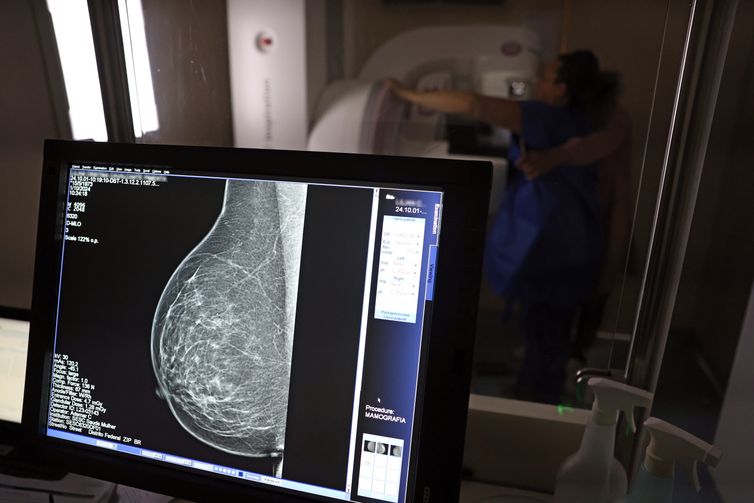

Câncer de mama: uma em cada três pacientes tem menos de 50 anos

Faixa etária concentrou 22% das mortes pela doença entre 2018 e 2023, segundo dados do Painel Oncologia Brasil.

Dados do Painel Oncologia Brasil, analisados pelo Colégio Brasileiro de Radiologia e Diagnóstico por Imagem (CBR), indicam que mais de 108 mil mulheres com menos de 50 anos foram diagnosticadas com câncer de mama no Brasil no período entre 2018 e 2023 – uma média de uma em três mulheres diagnosticadas com a doença.

Para a entidade, os números reforçam a importância de ampliar o rastreamento do câncer de mama por meio da realização de mamografia em mulheres abaixo dos 50 anos e acima dos 70 anos, faixas etárias que não estão incluídas na recomendação padrão de exames preventivos no âmbito do Sistema Único de Saúde (SUS). >> Siga o perfil da Agência Brasil no Instagram